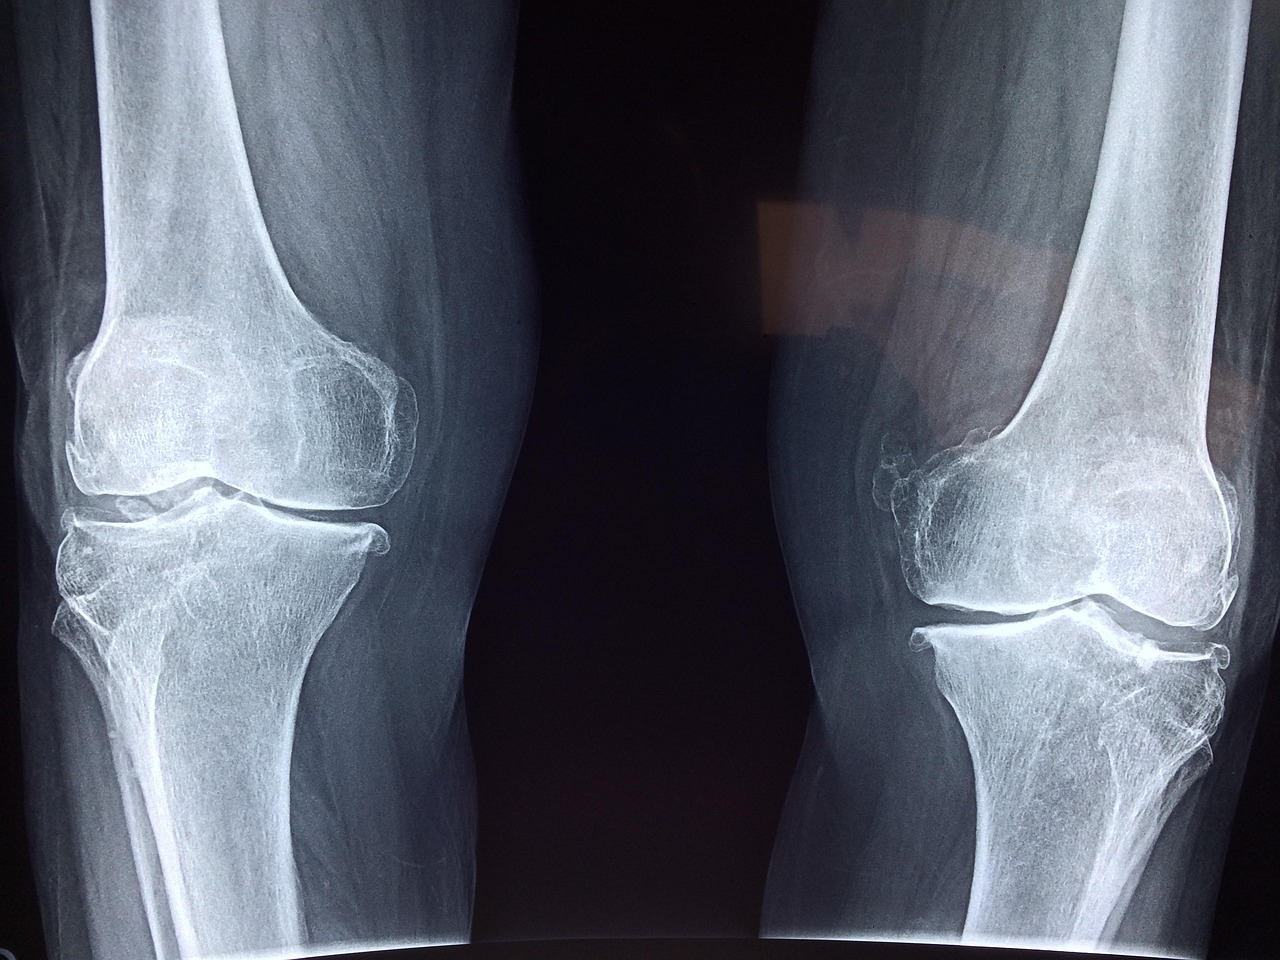

Aging is a natural process that can impact men’s bone health significantly. As men age, their bodies produce less testosterone, which can lead to decreased bone density. Usually, men are at risk of osteoporosis, often misperceived as a women’s issue. Hence, awareness of osteoporotic signs, such as frequent fractures, should be prioritized. To counteract these changes, men should incorporate resistance training and stimulate testosterone production naturally via physical activity. Regular weight-bearing exercises help maintain bone strength. Furthermore, ensuring an intake of adequate protein is essential; protein plays a crucial role in bone health by aiding in the formation and maintenance of bone tissue, which is vital as one ages. Regular medical screenings can assist in monitoring bone health and assist in outlining specific dietary and lifestyle changes necessary for improved bone density. Men should consult their healthcare provider on effective supplementation, particularly vitamin D, to maximize calcium absorption. Moreover, understanding individual health history and family backgrounds is essential. Strategies like adopting a bone-healthy lifestyle will actively improve men’s bone health and facilitate independence into older adulthood.